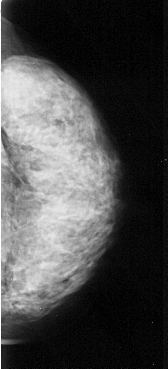

A_1000_1.LEFT_MLO

LEFT_MLO LINES 4861 PIXELS_PER_LINE 2521 BITS_PER_PIXEL 16 RESOLUTION 42 OVERLAY

FILE: A_1000_1.LEFT_MLO.OVERLAY

TOTAL_ABNORMALITIES 1

ABNORMALITY 1

LESION_TYPE CALCIFICATION TYPE PLEOMORPHIC DISTRIBUTION CLUSTERED

ASSESSMENT 4

SUBTLETY 2

PATHOLOGY MALIGNANT